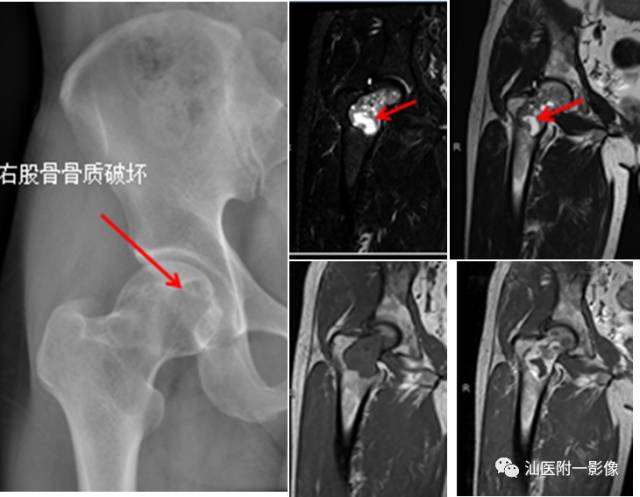

•软骨母细胞瘤为来源于幼稚软骨细胞(软骨母细胞)。

•常见于青少年,多发生于10~20岁之间。

•多发生于四肢长骨,以胫骨、股骨和肱骨多见。

•软骨母细胞瘤的溶骨区常常开始位于骨骺,倾向于越过骨骺线,向干骺端蔓延。